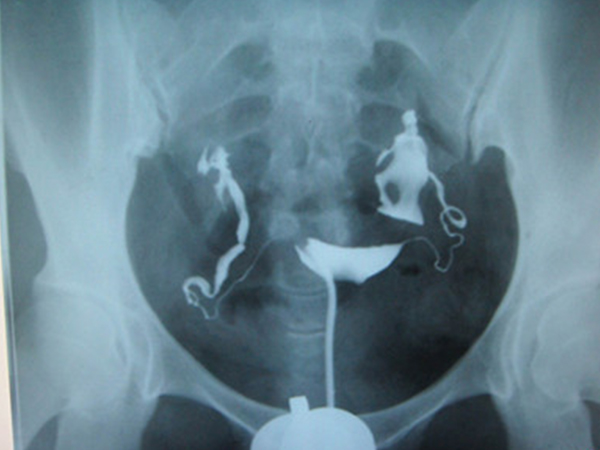

别跟风输卵管造影,不知道这些副作用前不要轻易做

输卵管造影主要针对的是有不孕不育、输卵管堵塞、子宫发育畸形等问题女性,因此在进行妇科检查的时候跟风做该检查,因为输卵管造影存在一定的副作用,没有大问题的女性是不..

hpv和tct两种检查虽然检查项目不一样但都是能够筛查女性早期宫颈癌变的手段,HPV是以检查病毒为主而TCT是以检查细胞为主,二者的关系其实就是病因和结果的关系,在临床上很..